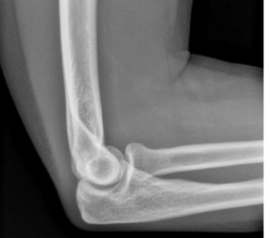

What is this

normal elbow